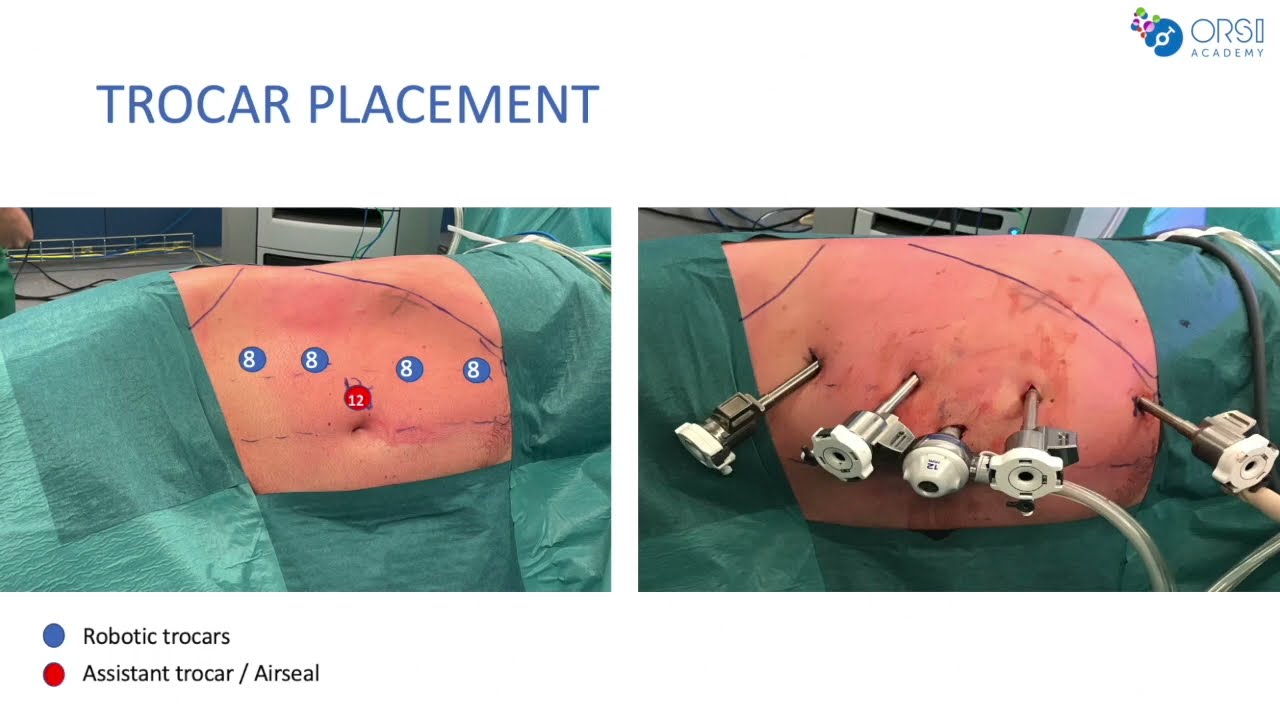

Port Placements by Indian (Manipal) Modification for da Vinci X Surgical System

Gynecology, Oncology ';